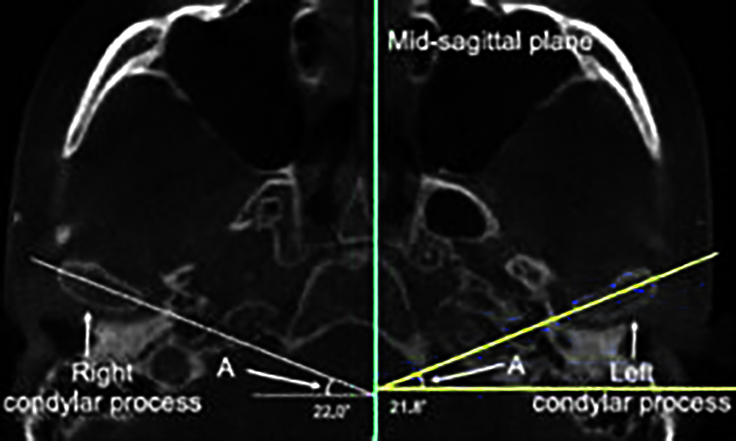

Рис. 5. Аксиальный угол мыщелка.

Значения аксиального угла мыщелка у пациентов исследуемых групп представлены на рис. 5 и в табл. 3.

В группе пациентов с гнатической формой мезиальной окклюзии и симметрией нижней челюсти разница значений аксиального угла между правой и левой сторонами и в группе пациентов с гнатической формой мезиальной окклюзии и симметрией нижней челюсти разница значений аксиального угла между девиирующей и недевиирующей сторонами вычислялась посредством вычитания значения на недевиирующей стороне из значения на девиирующей стороне. Разница значений была значительно больше в группе пациентов с гнатической формой мезиальной окклюзии и асимметрией нижней челюсти по сравнения симметричной группой (табл. 4).

Рис. 6. Увеличение аксиального угла на девиирующей стороне.

Как следует из табл. 4, на девиирующей стороне в группе пациентов с гнатической формой мезиальной окклюзии и асимметрией нижней челюсти значение аксиального угла мыщелка значительно больше, а также абсолютное значение разницы демонстрирует тенденцию к увеличению значения аксиального угла мыщелка на девиирующей стороне у пациентов асимметричной группы (рис. 6).

Увеличение аксиального угла мыщелка на девиирующей стороне у пациентов асимметричной группы свидетельствует о том, что пациенты с гнатической формой мезиальной окклюзии и асимметрией нижней челюсти имеют билатеральную разницу в аксиальной ориентации мыщелков по сравнению с пациентами с симметрией нижней челюсти, причем аксиальный угол значительно больше на стороне девиации.